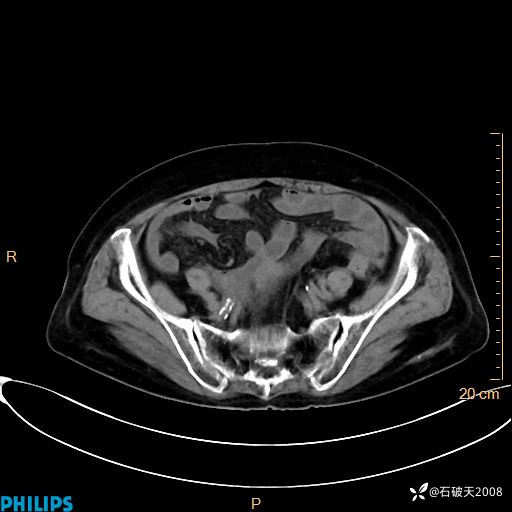

静脉期